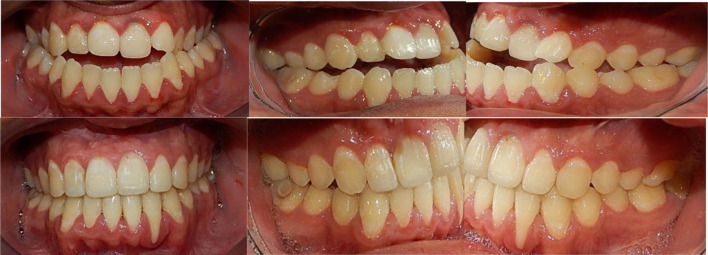

Fig. 22.

Pre-operatory and post-operatory dental occlusion. The patient was treated at the Centro de Estudios Superiores de Ortodoncia (CESO by Dr. Maria Angelica Sanchez Contreras)

Fig. 25.

Preop and postop dental occlusion

The result after the orthognathic surgery can be seen in the frontal and lateral views. The facial physiognomy was improved, as well as the dental occlusion which went from a class III to class I (Figs. 28, 29).

Fig. 28.

Preop and postop photographs side by side, demonstrating surgical outcome

Fig. 29.

Preop and postop photographs of dental occlusion, side by side